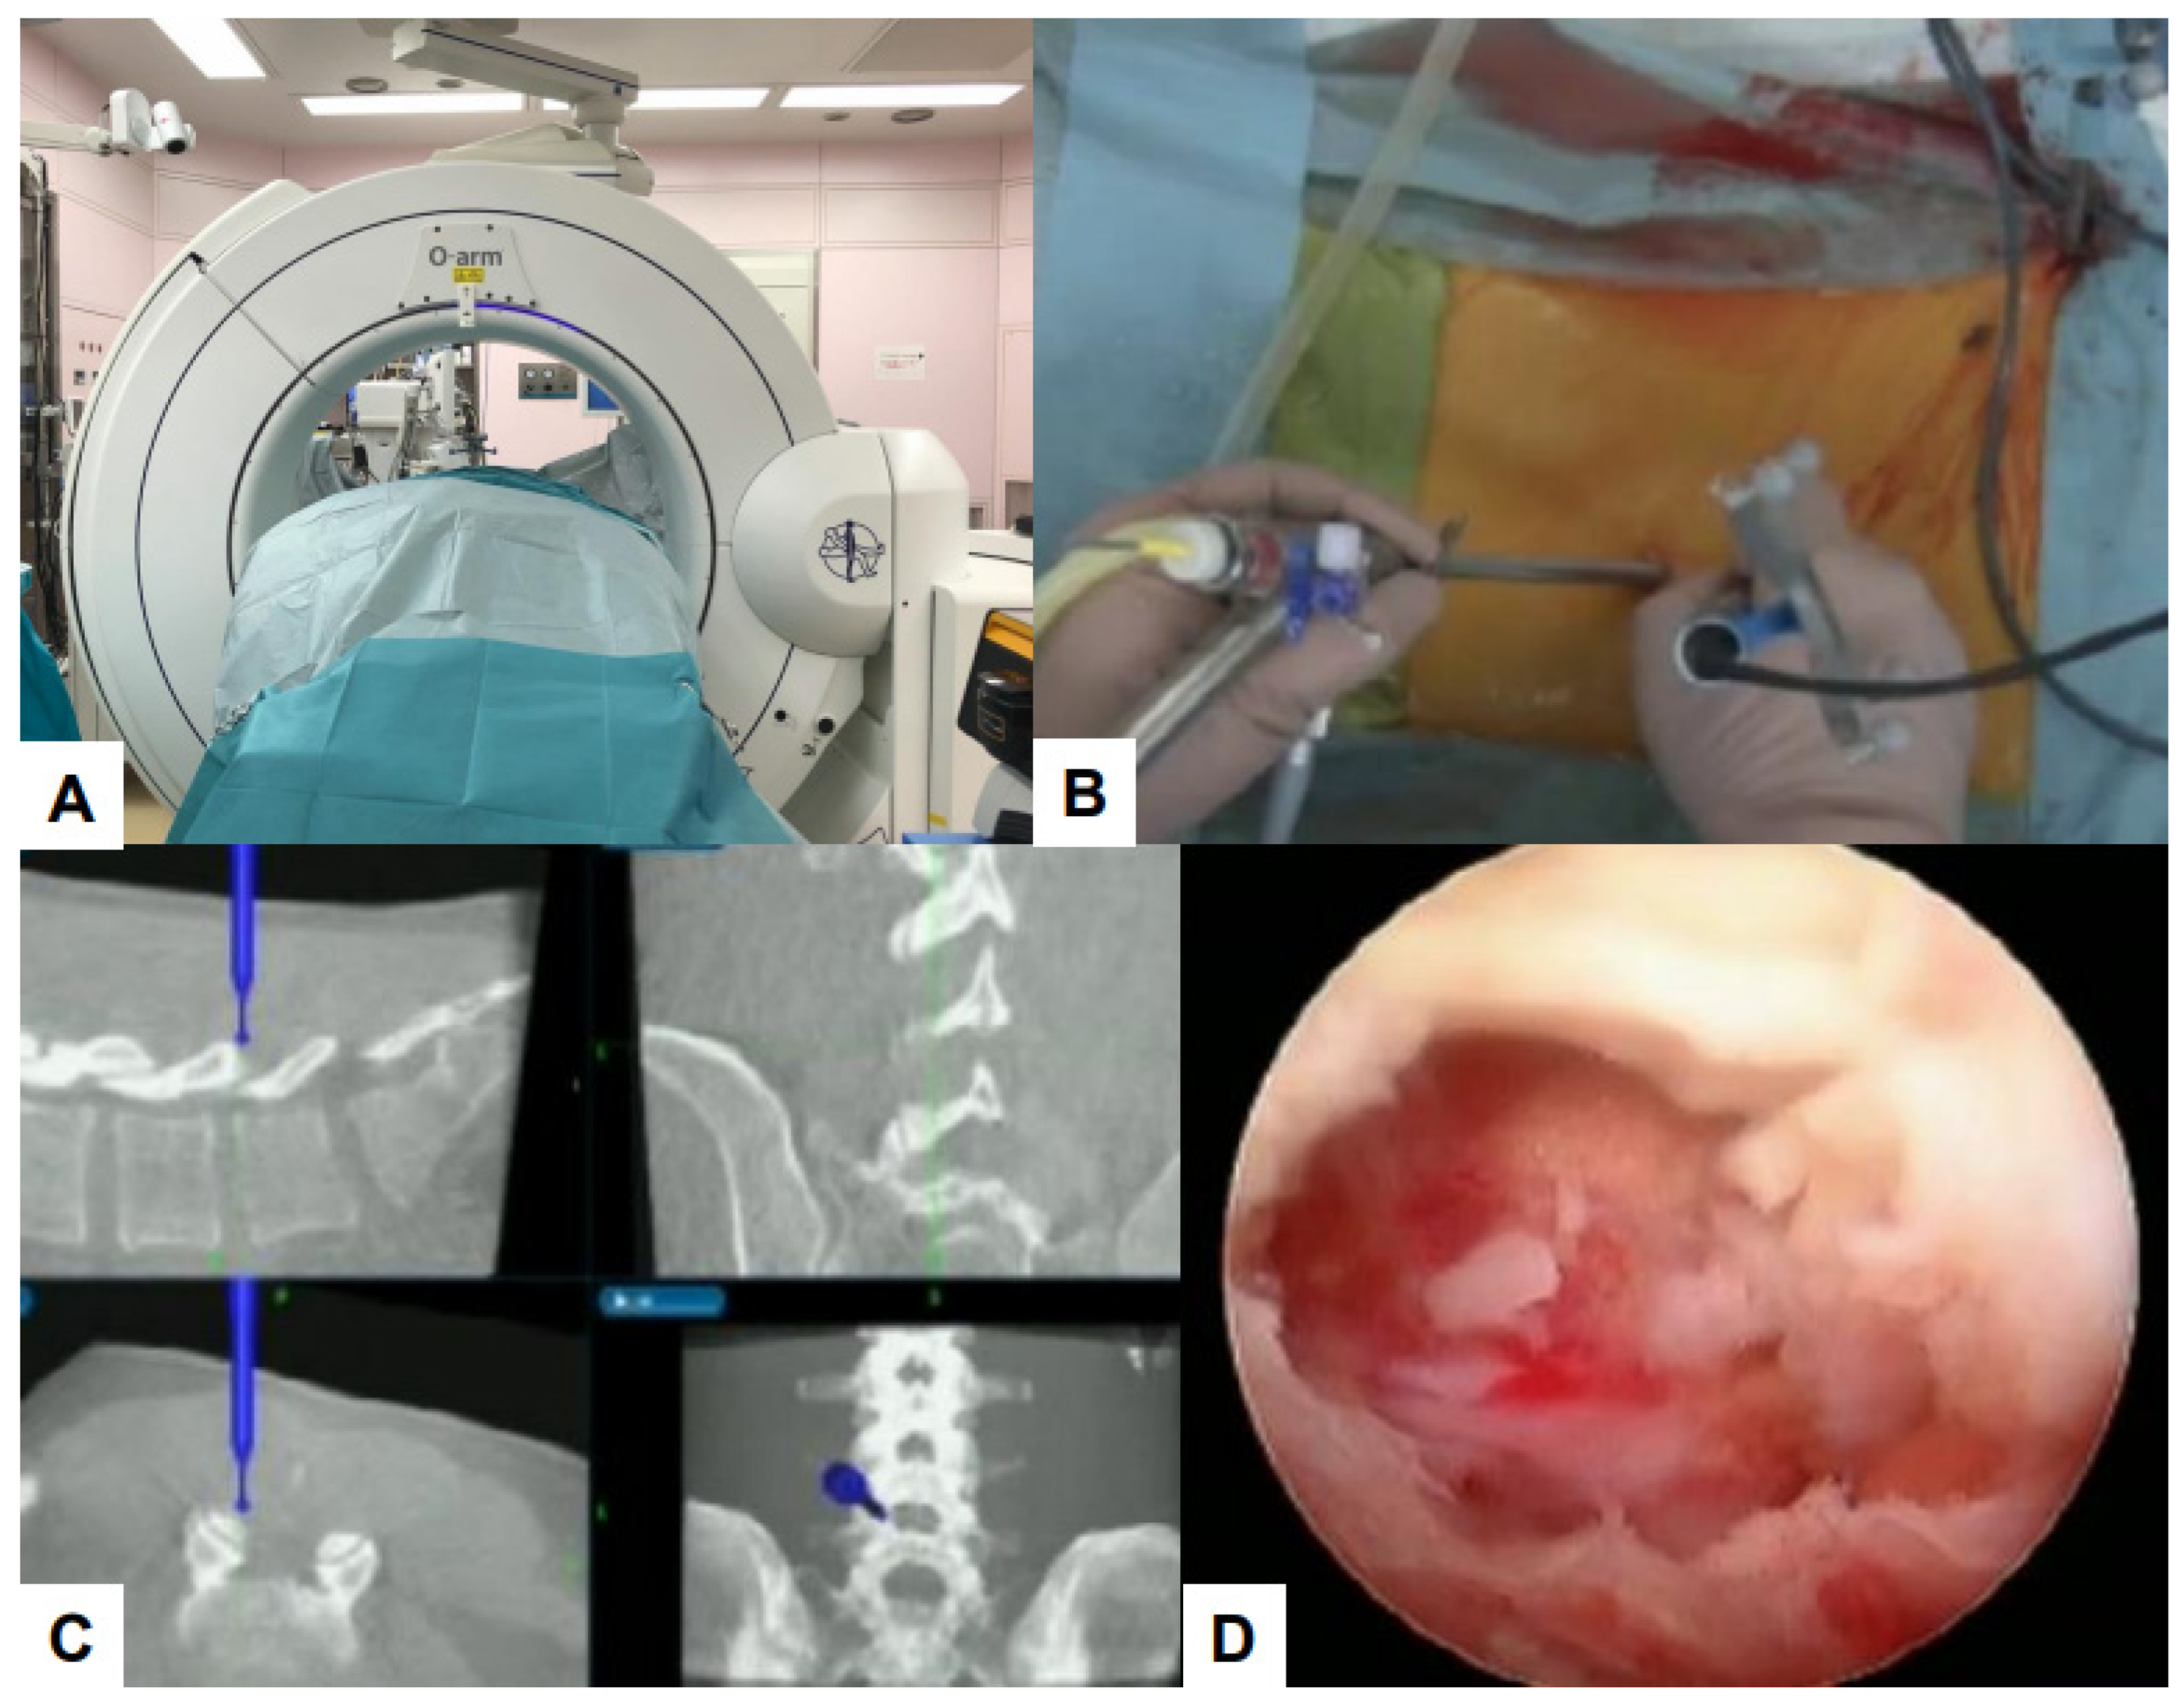

7. Latest Advances

7.1. Navigation